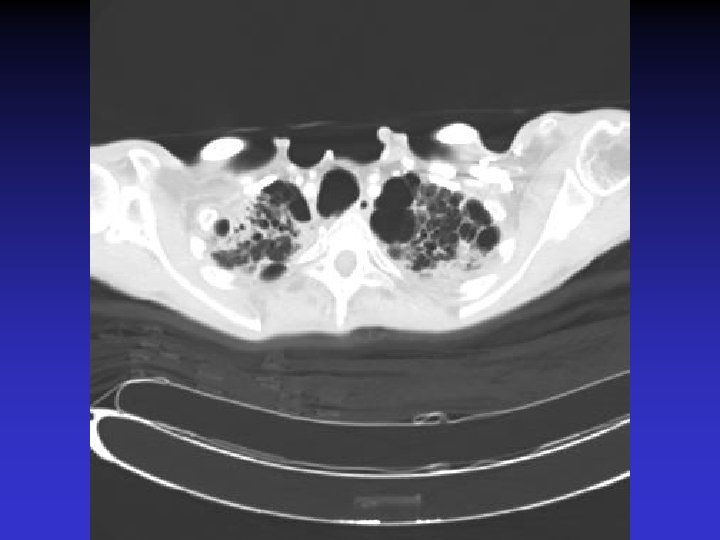

NTM lung disease n n MAC, M. kansasii, M. abscessus >50 years, ? M vs. F Symptoms n variable, nonspecific n chronic or reoccurring cough n sputum production, fatigue, malaise, dyspnea, fever, hemoptysis, chest pain, wt loss n more constitutional symptoms with advancing disease n evaluation complicated by sx of coexisting lung disease CXR n Fibrocavitary – often like MTB, but may be dense airspace dz or solitary cavity w/o cavitation n Nodular/bronchietatic – typical MAC, usu. mid-lower lung fields, +/- cavitation

M. simiae n n M. simiae may be confused with MTB as it is the only niacin-positive NTM Maoz et al. compared pts in Israel with M. simiae vs MTB. Pts with M. simiae: n More females, older age n Higher rates of smoking, COPD, other dz (DM, CAD, cancer), immunosuppressive drugs n Less HIV n Blunted symptoms n More noncavitary infiltrates in middle/lower lobes Most M. simiae isolates were contaminants Treatment with clarithromycin, ethambutol, rifabutin, and streptomycin (with modification for sensitivities)